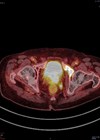

A 72-year-old gentleman is referred to you in the two-week wait clinic with a prostate specific antigen (PSA) of 22ug/L. He is otherwise fit and well and does not take any regular medication. His multi-parametric magnetic resonance imaging (mpMRI) shows...